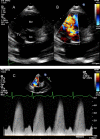

This review article will guide the reader through the basics of echocardiographic assessment of congenital left to right shunts in both paediatric and adult age groups. After reading this article, the reader will understand the pathology and clinical presentation of atrial septal defects (ASDs), ventricular septal defects (VSDs), atrioventricular septal defects (AVSDs) and patent arterial duct. Echocardiography is the mainstay in diagnosis and follow-up assessment of patients with congenital heart disease. This article will therefore describe the echocardiographic appearances of each lesion, and point the reader towards specific features to look for echocardiographically.